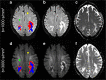

Objectives: An ill-defined hyperintense edge and hypointense core on diffusion-weighted imaging (DWI) is typical of progressive multifocal leukoencephalopathy (PML). We aimed to investigate whether a b-value of 3,000 s/mm2 (b3000) can improve visualisation of PML, or provide different structural information compared to 1,000 s/mm2 (b1000).

Results: Nine lesions from seven patients were analysed. The rim and core were better visualised on b3000, with higher signal of the rim and lower signal of the core compared to NAWM. The hyperintense rim had non-restricted average ADCs, but included foci of low ADC on both b3000 and b1000. Despite similar total lesion volumes, b3000 displayed significantly larger core and smaller rim volumes than b1000.

Conclusion: b3000 improves visualisation of this important PML hallmark. Moreover, b3000 partly reclassifies tissue from rim into core, and might provide potentially more accurate biomarkers of PML activity and prognosis.

Key points: • B3000 improves contrast resolution between lesion rim, core and normal-appearing white matter. • B3000 improves identification of the typical rim-and-core pattern of PML lesions. • B3000 and b1000 similarly identify lesions, but b3000 results in smaller rims and larger cores. • B3000 excludes some high diffusion components from rim, reclassifying them into core. • B3000 DWI may provide more precise PML biomarkers of disease activity and tissue damage.